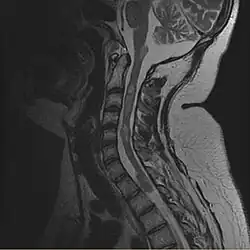

- wyściółczaki (2,5%)[8]. Glejaki włosowatokomoórkowe (gąbczaki) i wyściółczaki zwykle są zlokalizowane w pniu mózgu i górnym odcinku szyjnym rdzenia kręgowego; często współwystępują z jamistością rdzenia lub opuszki. Niekiedy uciskają rdzeń.

- MRI mózgowia i rdzenia ze wzmocnieniem kontrastowym.